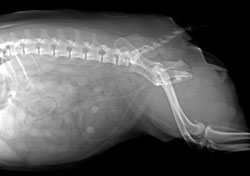

#11 Two struvite bladder stones were forgotten after surgery in this 6-year-old female pug.

Postoperative radiographs should be taken when appropriate, for example after fracture repair or after a cystotomy. Some specialists consider it wise to check that all bladder stones have in fact been removed. Likewise, ensuring that a cystotomy or perineal urethrostomy patient can urinate before going home is a wise precaution.